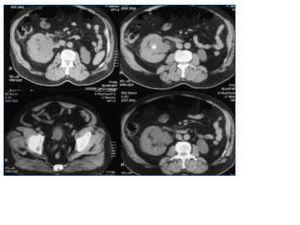

Una semana antes del ingreso sufre cólico nefrítico derecho que se trata con antiinflamatorios no esteroideos (meloxicam). Acude a urgencias por oligoanuria de 24 horas de evolución sin fiebre ni hematuria. En la analítica destaca insuficiencia renal severa (Cr 7 y urea 167 mg/dl). La ecografía muestra riñón derecho de 13,5 cm, con litiasis en polo inferior y pelvis (17 y 15 mm respectivamente) y ausencia de riñón izquierdo. La TAC abdominal confirma las litiasis y muestra además dilatación del uréter distal con litiasis en meato ureteral derecho y atrofia cortical del riñón izquierdo (fig. 2). Se inicia tratamiento con sueroterapia y diuréticos sin lograr diuresis. Tras fracasar el intento de cateterismo ureteral y desestimar la nefrostomía por insuficiente dilatación de la pelvis se coloca catéter venoso central y se realiza hemodiálisis. A pesar de la hidratación no se observa incremento de la dilatación urinaria que permita realizar una nefrostomía percutánea, por lo que se decide administrar rasburicasa (0,20 mg/kg/día) durante 2 días, observando a las 6 horas recuperación brusca de la diuresis, recogiendo esa noche 6 litros de orina, manteniendo poliuria decreciente en días posteriores y con rápida mejoría de la función renal lo que permite suspender la hemodiálisis (fig. 3). Una nueva TAC abdominal realizada días más tarde mostró desaparición de la litiasis del meato ureteral derecho.

Figura 2.